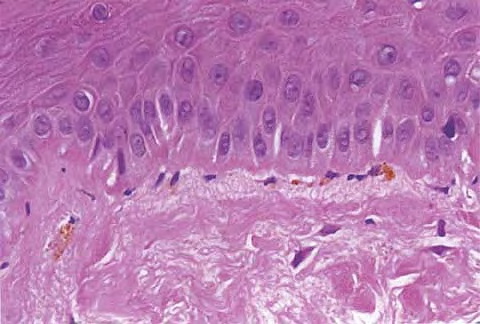

Discoid LE= الذئبة الحمامية القرصية